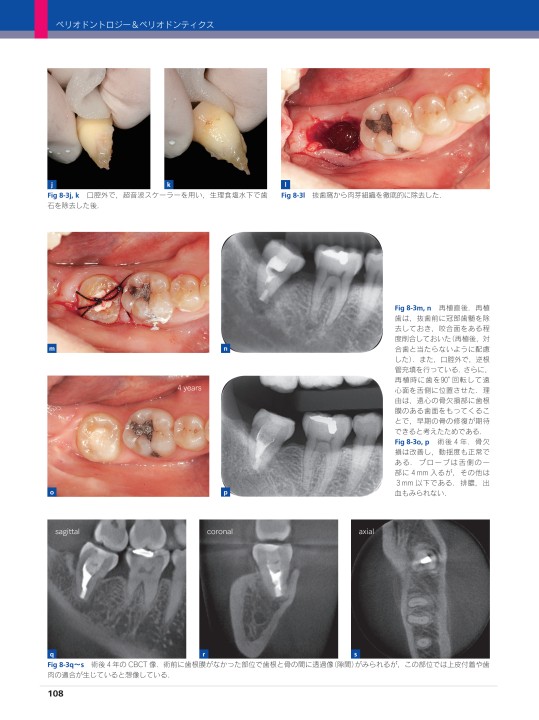

裁断済です。裁断しているので全体的に状態画悪いとしております。\r\r歯科臨床に基づくペリオドントロジーの専門書。\r\r- タイトル: ペリオドントロジー&ペリオドンティクス\r- シリーズ名: シリーズ MIに基づく歯科臨床\r- 巻番号: 05\r- 出版社: クインテッセンス出版\r- 著者: 月里光博\r\rご覧いただきありがとうございます。